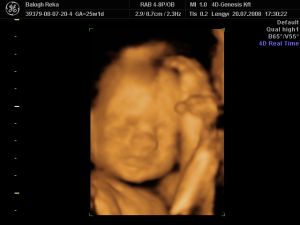

Na de a lényeg. A 4D szupi volt, megint aranyos volt a Márta. Onnan mentek egyből nyraalni, a férje kint várt rá, tök rendes volt tőle, h miattam azért bejött. Azért picit lehetett érezni, h jobban sietett, mint múltkor, meg aludt a baby, és nem ébreszgettük...de azért így is lettek nagyon jó képek. Azért gondolom nyugisabb körülmények között belefért volna egy séta, meg csokievés, ugrabugra, miegymás. De sabaj, a lelkemre kötötte, h mindenképp szóljak, h mi lett a vesémmel, mielőtt megyünk vissza, meg is akarja nézni, mondta, h mindenképp ugorjak be majd ha tudok. Hát én asszem úgy döntöttem, h jövő szerdán amúgyis el akarok menni még egy mozira is, mert szeretnék egy jókis mozgós felvételt, felébresztjük, bármi áron. :) Mert nekem már valszín nem lesz lehetőségem többet látni a kiscsajt, úh szeretnék még egy jó kis aktív mozit amúgyis. :) Talán még aug végén tudok jönni, de ez még nagyon nagyon kérdéses...

És akkor jöjjön a lényeg. :) Egyébként én tökre meglepődtem, h ennyire pufi már 25 hetesen. Én nagyon sok 4D-s képet nézegettem a neten, és 30hét és afelett szoktak már ilyen pufik lenni a babyk...na kiváncsi vagyok majd élőben... :)